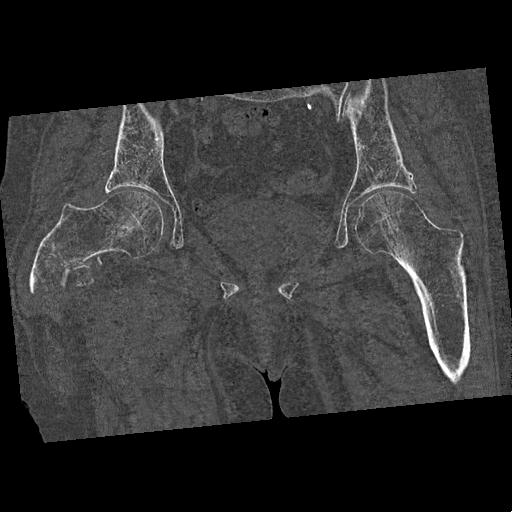

100703 1/27 両股正面+軸 1/29 両股正面+軸 94歳女性 パンソンロン